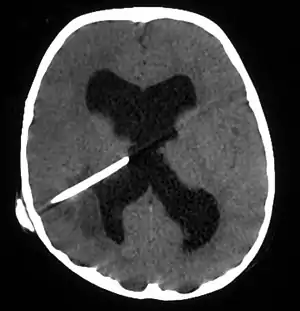

| آبسه مغزی در یک بیمار دارای شانت مغزی[1] | |

- Jamjoom et at. , ۲۰۰۹ Brain abscess formation as a CSF shunt complication: a case report. Jamjoom AA, Waliuddin AR, Jamjoom AB. Cases J. ۲۰۰۹ Jan ۳۱;۲(۱):۱۱۰. PMID 19183497